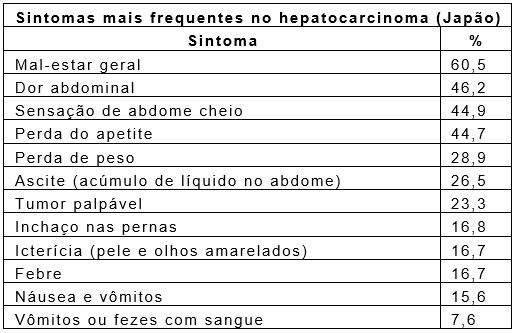

No início, mesmo a cirrose pode ser silenciosa (cerca de 40% dos casos). Os sintomas mais comuns são fraqueza, fadiga, perda do apetite, emagrecimento, hematomas e sangramentos espontâneos, irregularidade menstrual, icterícia (pele e olhos amarelados, pelo acúmulo de bile no sangue) e dificuldade de manter a concentração. Também podem ser mais graves, como o coma, vômitos com sangue e ascite (acúmulo de líquido no abdome).

O hepatocarcinoma é um tumor altamente maligno, que dobra o seu volume a cada 180 dias em média. Mesmo em seu estágio inicial, ou seja, um tumor pequeno, localizado em um fígado com bom funcionamento, dá ao seu portador apenas cerca de oito meses de vida após ser encontrado, se não for realizado nenhum tratamento. No estágio mais avançado, a previsão média é de menos de três semanas de vida após o diagnóstico. Daí a necessidade do diagnóstico precoce do hepatocarcinoma, quando este ainda tem boas opções de tratamento e chance de cura.

Esse tipo de câncer cresce silenciosamente nos canais biliares até que estes sejam obstruídos, levando aos sintomas de icterícia, fezes claras e urina escura, além de perda do apetite e emagrecimento. Ocasionalmente, pode ser descoberto em exames de rotina ou durante o acompanhamento de pacientes com colangite esclerosante primária.